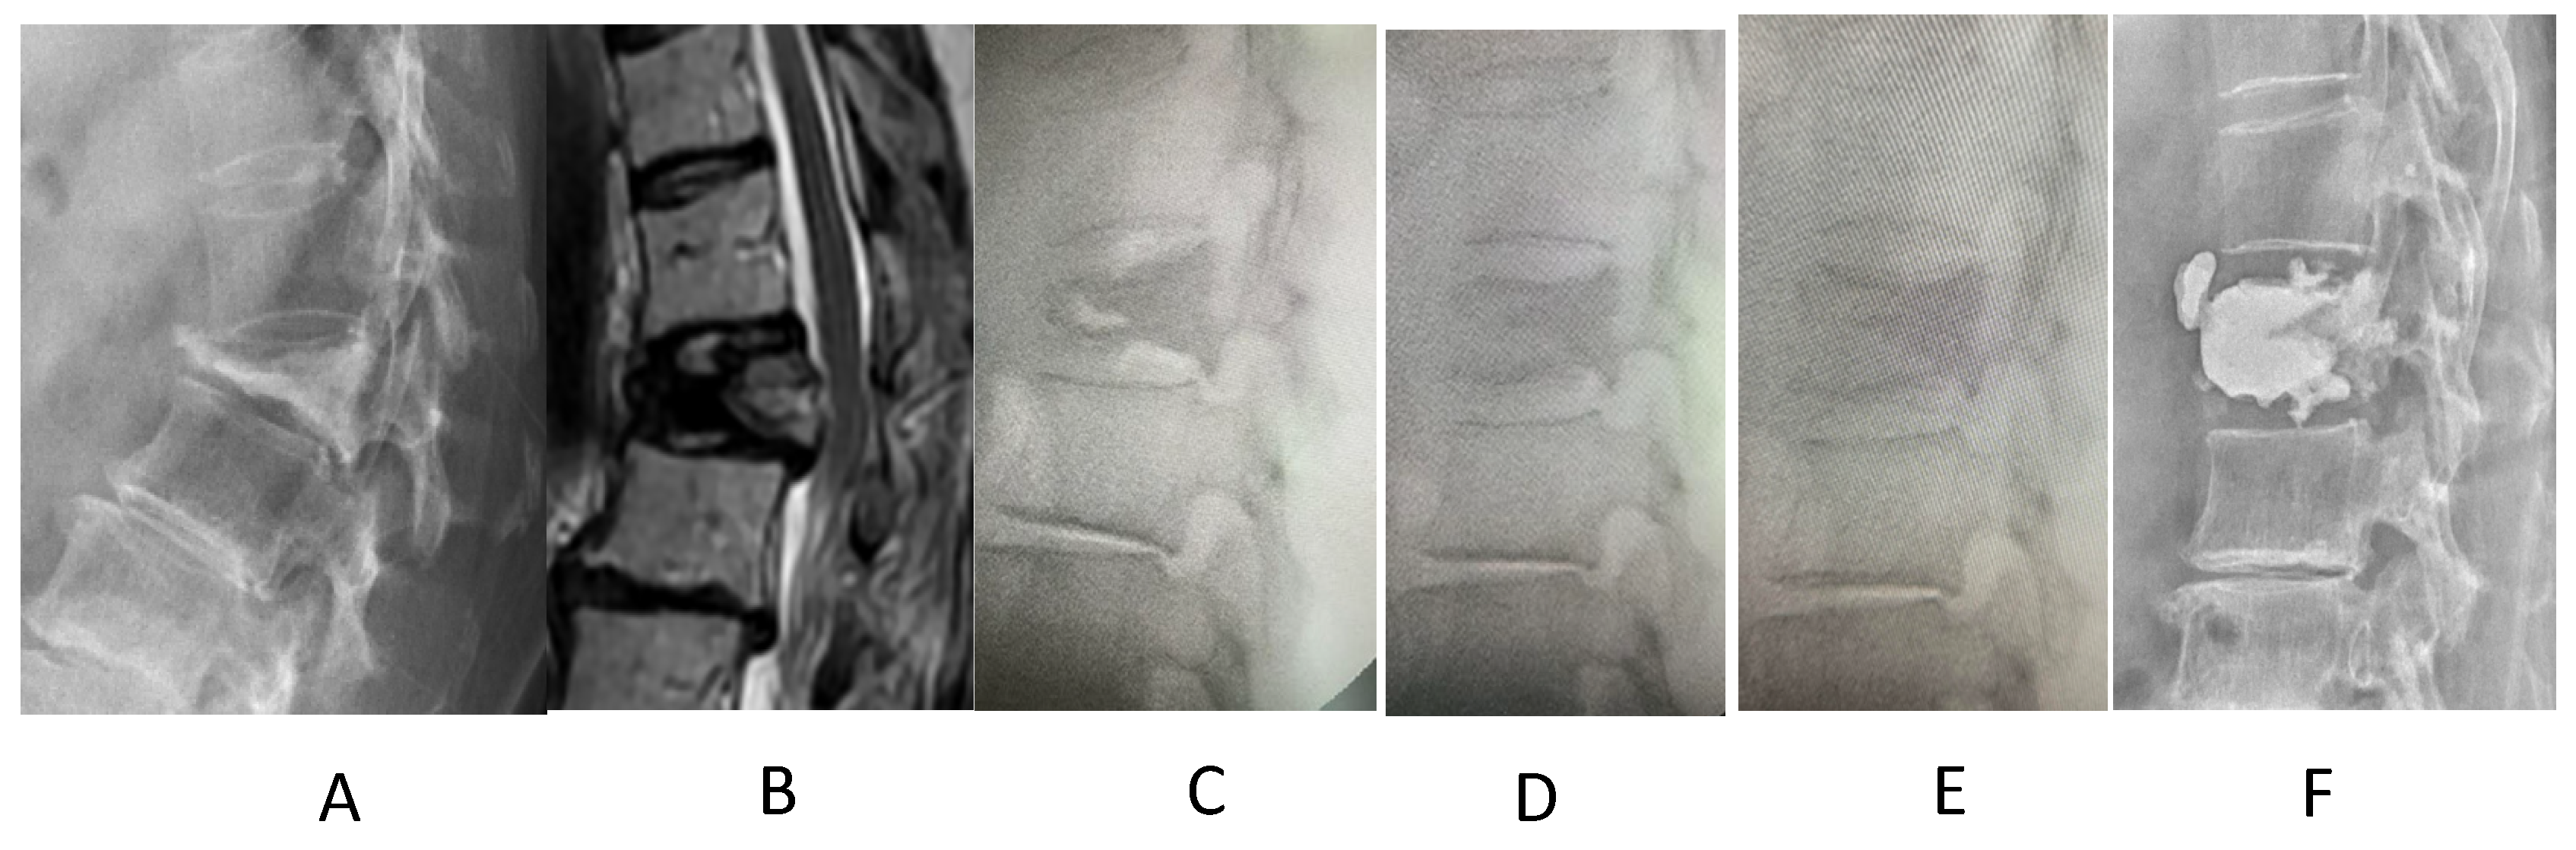

2. Materials and Methods

3. Results

4. Discussion